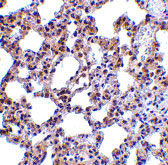

Immunohistochemistry of PKR in rat lung tissue with PKR antibody at 5 μg/mL. |